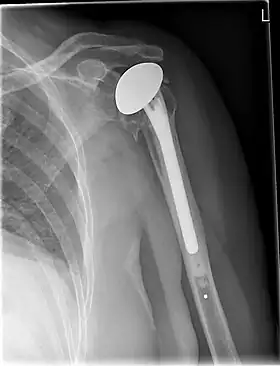

![]() X-ray of a shoulder prosthesis | |

Shoulder replacement is a surgical procedure in which all or part of the glenohumeral joint is replaced by a prosthetic implant. Such joint replacement surgery generally is conducted to relieve arthritis pain or fix severe physical joint damage.[1]

Various materials can be used to make prostheses, however the majority consist of a metal ball that rotates within a polyethylene (plastic) socket. The metal ball takes the place of the patient's humeral head and is anchored via a stem, which is inserted down the shaft of the humerus. The plastic socket is placed over the patient's glenoid and is typically secured to the surrounding bone via cement.[11]